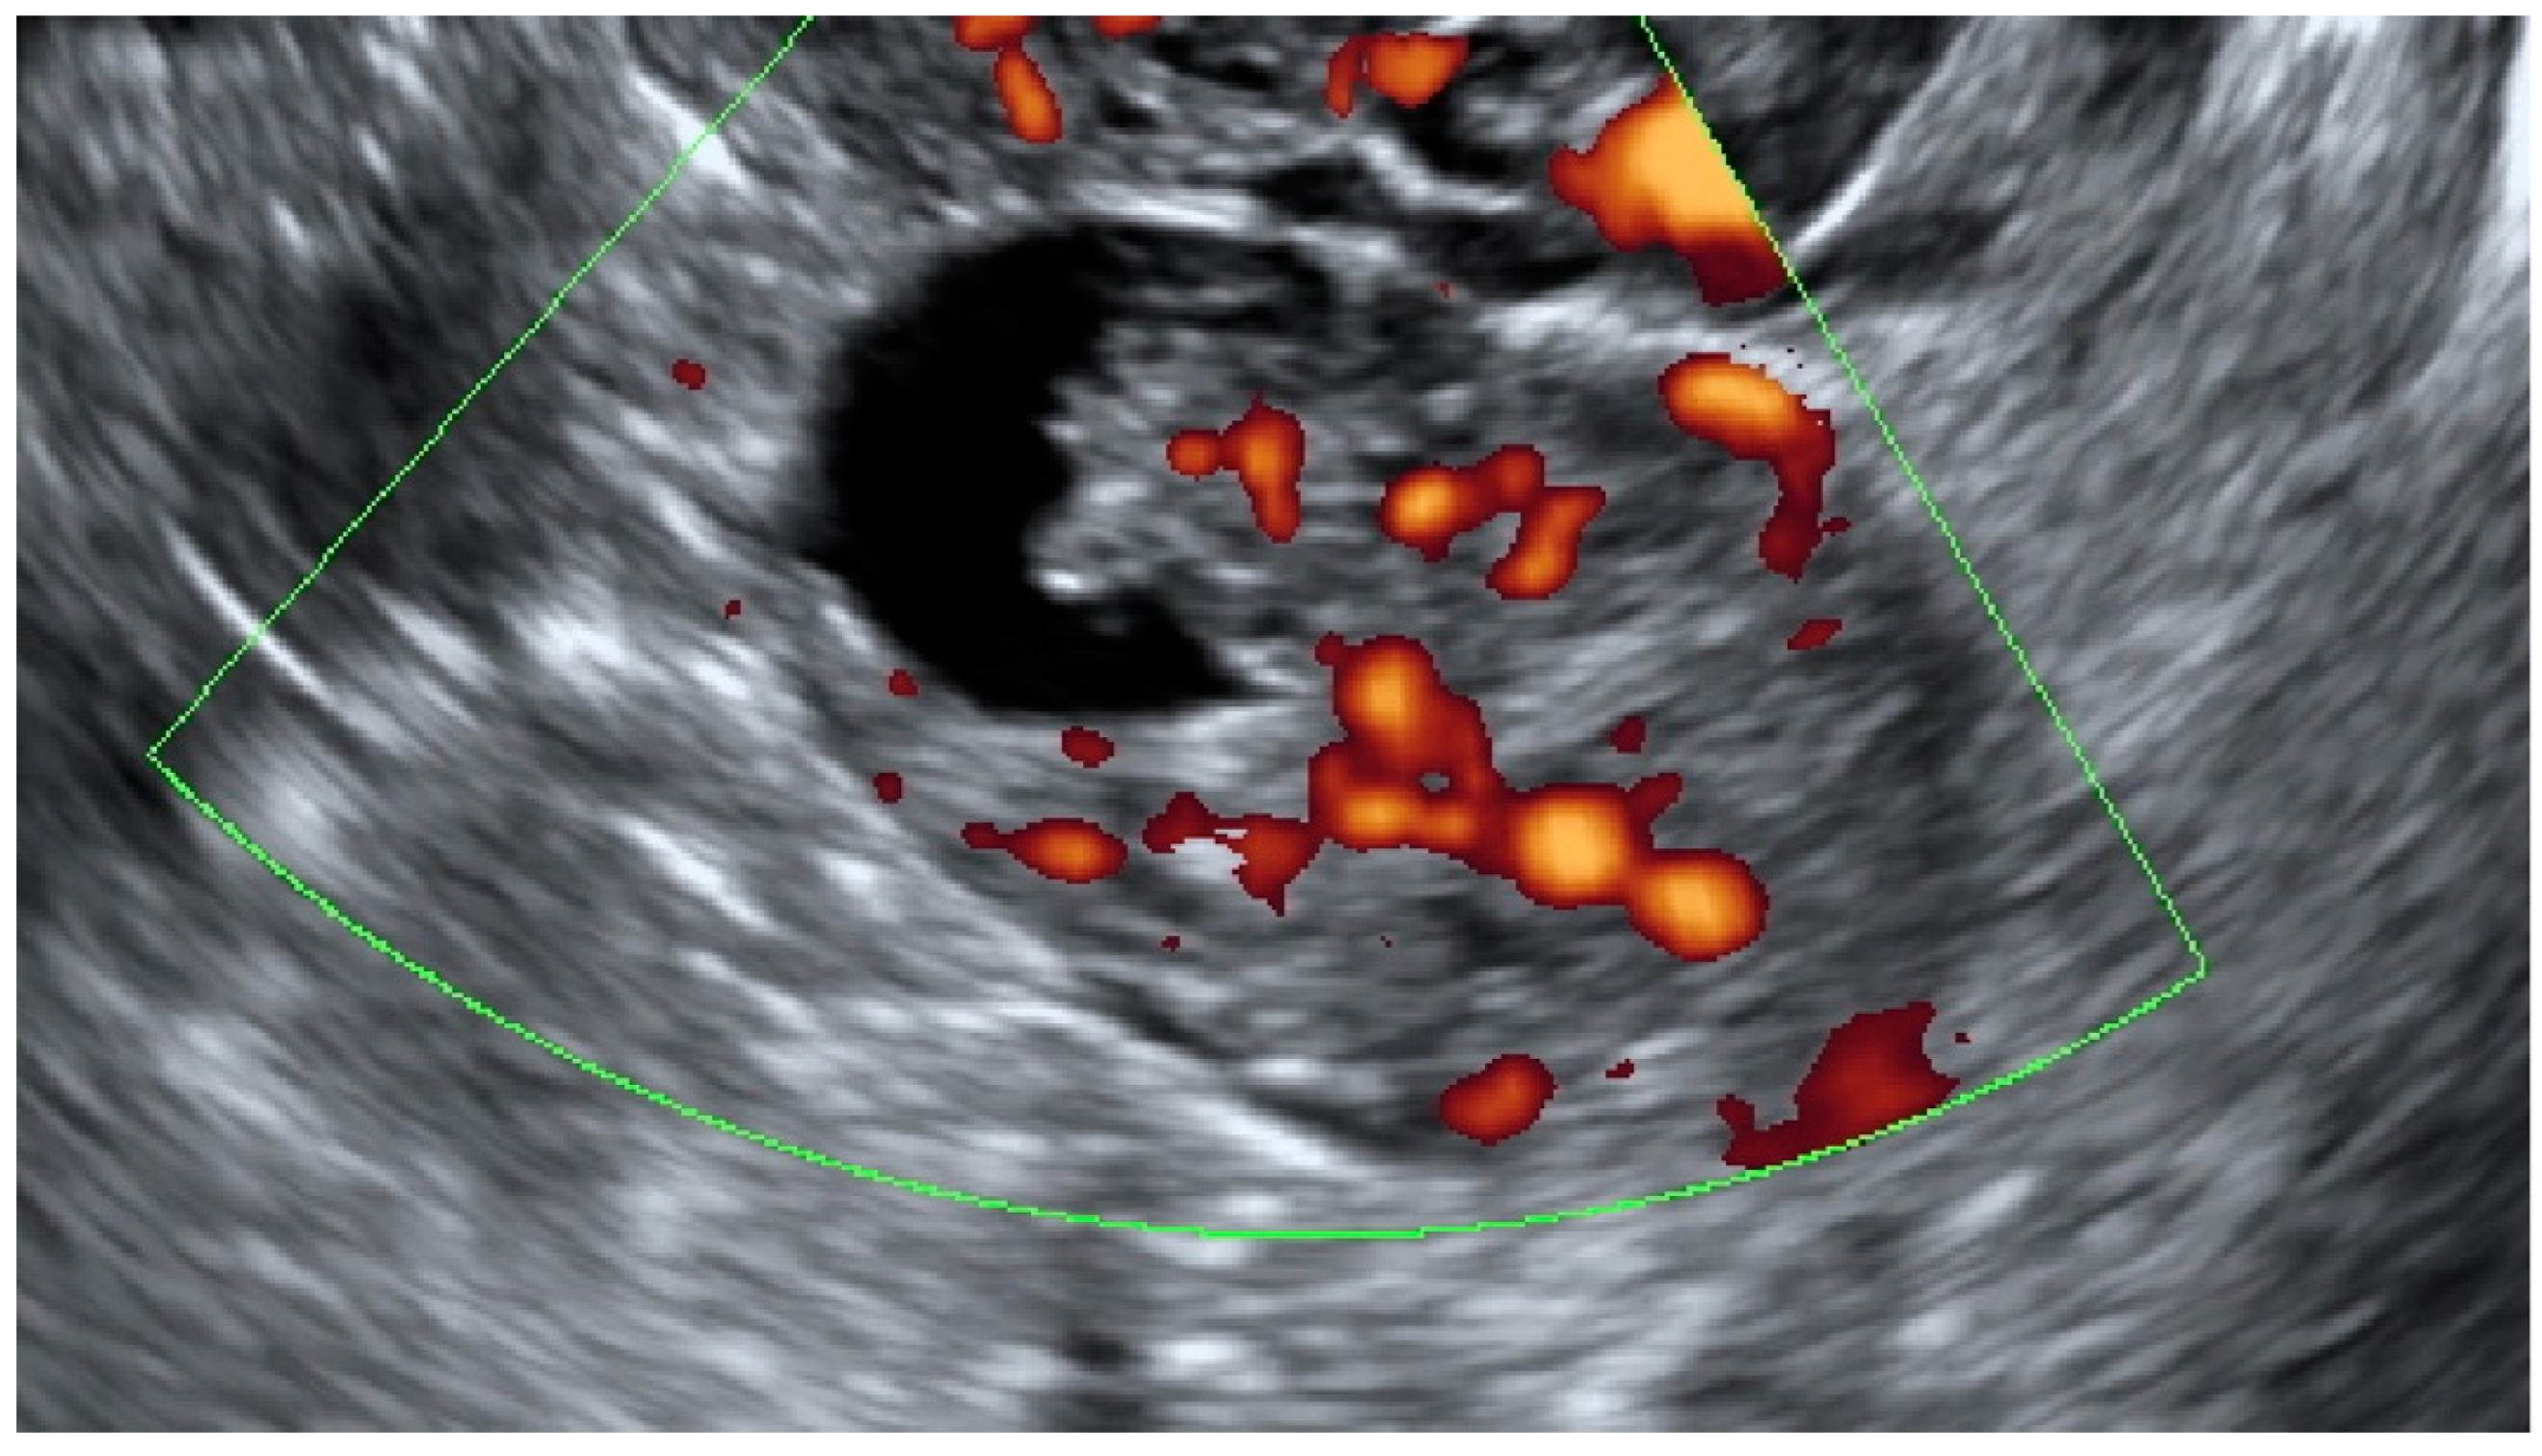

| Papillation flow | ||||

| Absent | 58 (93.6) | 21 (80.8) | 15 (75) | 0.05 |

| Present | 4 (6.4) | 5 (19.2) | 5 (25) | |

| Color Score | ||||

| 1 | 33 (53.2) | 6 (23.1) | 4 (20) | 0.0009 |

| 2 | 13 (21) | 13 (50) | 4 (20) | |

| 3 | 15 (24.2) | 5 (19.2) | 8 (40) | |

| 4 | 1 (1.6) | 2 (7.7) | 4 (20) |